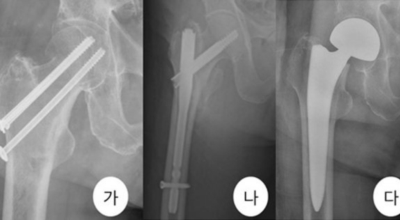

고관절 통증 증상 치료법

고관절 통증 치료에는 크게 약물 치료와 물리 치료가 있습니다. 고관절염의 진행을 늦추거나 증상을 완화하기 위한 목적으로 항염증제 및 진통제를 투여합니다. 고관절 통증을 조기에 치료하면 약물치료 외에 물리치료로 약 50% 정도 큰 효과를 볼 수 있습니다. 게다가, 보통 고관절 증상 관리에 도움이 되는 요가, 수영, 스트레칭은 고관절 예방과 치료에 도움이 됩니다.